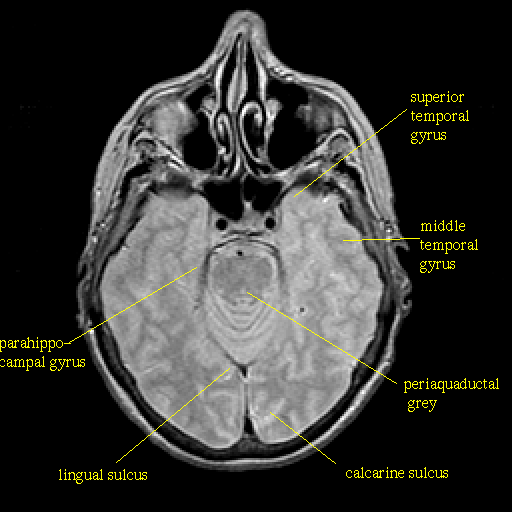

Proton density-weighted structural MR: Slice 18

Slice 18

Pointers

Labeled